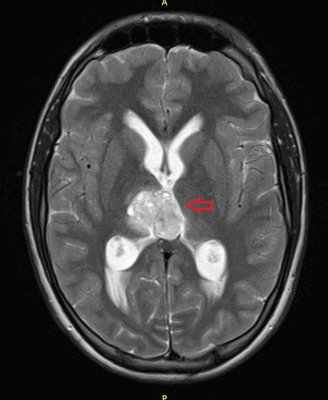

Головной мозг

Герминогенные новообразования в данной области - это примерно 2-4% от всех внутричерепных (интракраниальных). Патология в 75% случаев диагностируется у мальчиков, за исключением турецкого седла, где новообразования в основном локализуются у девочек.

Герминомы формируют инфильтрирующие опухоли больших размеров, часто являющиеся источниками субарахноидальных (между мягкой и паутинной оболочками мозга) и вентрикулярных (желудочковых) метастаз.

Рисунок 7. - Герминома головного мозга.

- КТ (расшифровка: компьютерная томография), МРТ (расшифровка: магнитно-резонансная томография), ПЭТ-КТ (расшифровка: позитронно-эмиссионная томография, совмещенная с КТ). Эти обследования необходимы, чтобы рассмотреть структуры организма послойно и визуализировать опухоль. Они показывают, как сильно распространен патологический опухолевый процесс на находящиеся рядом ткани и органы, есть ли поражение костей. КТ - это самый чувствительный метод для обнаружения метастазов в легких. Проведение МРТ и КТ головного мозга необходимо, чтобы обнаружить и визуализировать герминогенные новообразования эпифиза.

Рисунок 8. КТ органов брюшной полости - на снимках вы можете увидеть опухоль яичника.

Рисунок 9. - метастаз в головной мозг при герминогенной опухоли.

Также выполняют МРТ головного мозга, чтобы выявить наличие метастазов в нем.

![Метастаз в головной мозг при герминогенных опухолях (МРТ головного мозга)]()

Метастаз в головной мозг при герминогенных опухолях (МРТ головного мозга)

При дооперационном обследовании, и обязательно при высоком уровне ХГ или множественных метастазах в лёгкие, прибегают к МРТ головного мозга с контрастированием. В головном мозге при распространённом процессе могут существовать бессимптомные метастазы. Необходима КТ от шеи до малого таза, что позволяет выявить опухолевые отсевы и целенаправленно их разыскивать при операции, или вообще отказаться от операции в пользу химиотерапии при метастатическом поражении лёгких.